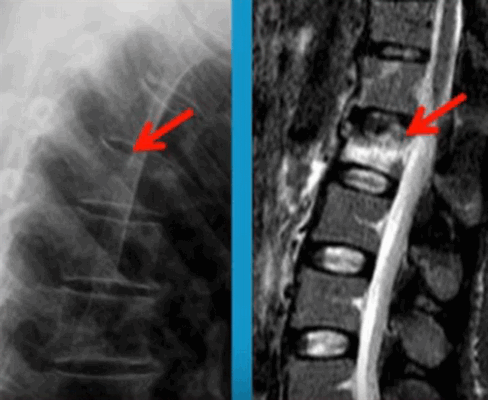

МРТ или КТ при переломе?

Перелом позвоночника (указан стрелками) на рентгене (слева) и при МР-сканировании (справа)

Компьютерная томография — это усовершенствованный вид рентгенографии. Отличие заключается в том, что КТ-аппарат делает множество снимков в аксиальной плоскости послойно, тогда как обычный рентген дает лишь суммарные изображения всей области интереса. Результаты КТ более информативны в плане диагностики переломов. Метод реагирует и отражает минимальное изменение плотности костной ткани. Недостатками КТ являются:

При отсутствии противопоказаний методом выбора для диагностики переломов считается КТ.